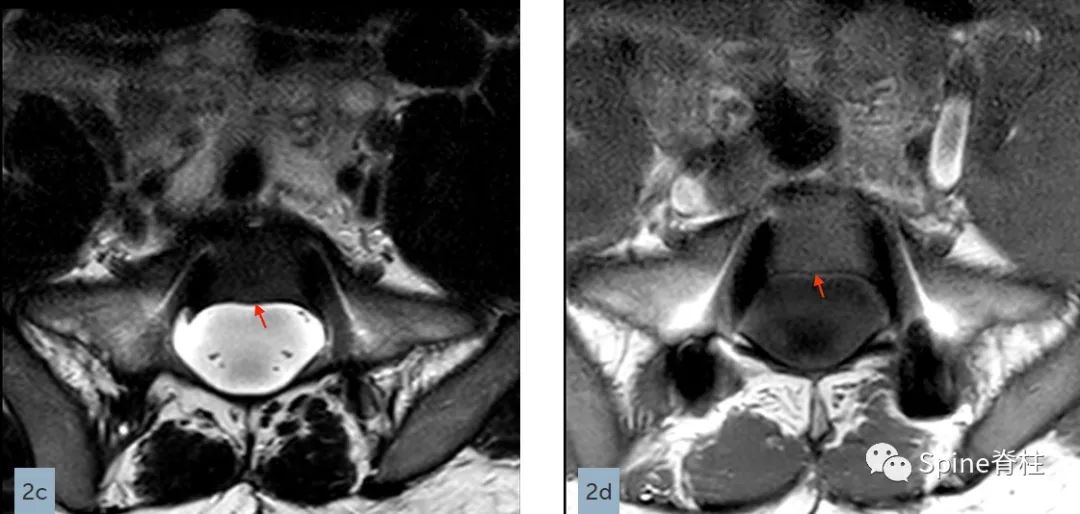

在矢状位T2(2a)和T1加权像(2b)上,多节段椎体后壁呈扇形缺损,缺少硬膜外脂肪(红色箭头),S1处的硬膜囊直径大于L4处。横断面T2(2c)和T1加权像(2d)提示硬膜囊膨胀,S1椎体后壁再次证实硬膜外脂肪缺失(红色箭头)。 其影像学表现符合硬膜扩张的诊断

矢状位T2(a)和T1(b)加权像提示下胸椎和上腰椎硬膜扩张伴显著的椎体后壁扇形凹陷(红色箭头)。轴位T2(c)和T1(d)加权像提示硬膜囊外侧膨出(绿色箭头)伴椎体扇形缺损。蓝色箭头是指继发于皮肤神经纤维瘤的多发性皮肤结节